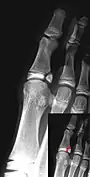

Salter–Harris I fracture of distal radius.

Salter–Harris II fracture of ring finger proximal phalanx.